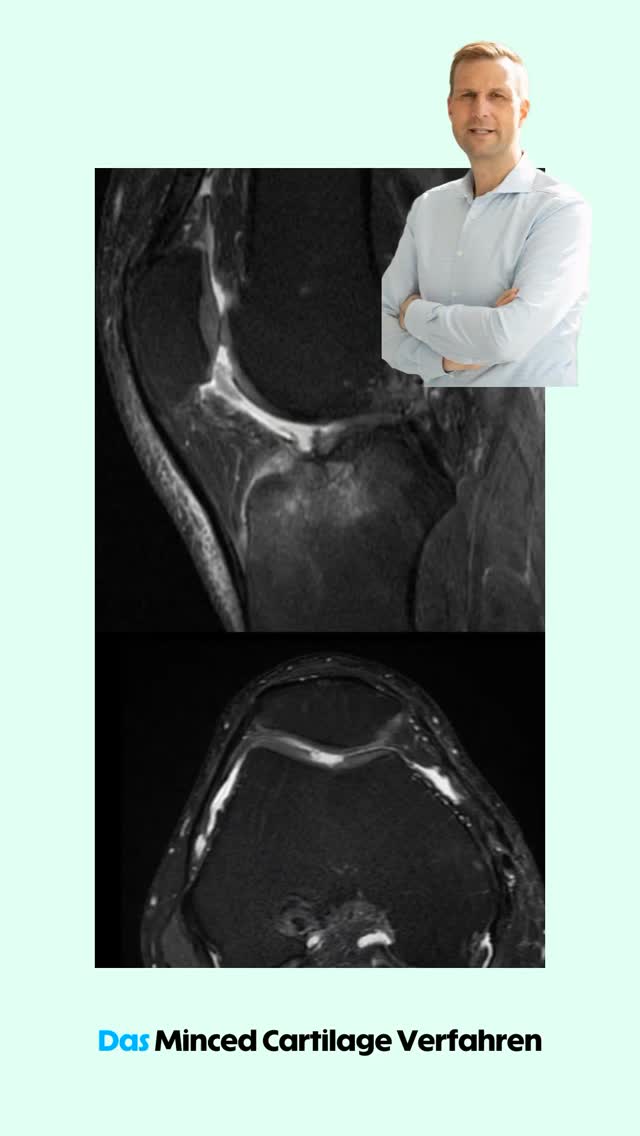

Knorpel - Gelenkerhalt- Arthrose